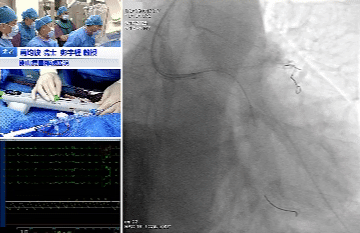

手术过程:

OAS处理前降支

OAS处理回旋支

术中造影提示第一、第二对角支开口严重狭窄,分别对前降支严重钙化病变、回旋支次全闭塞应用OAS进行旋磨等充分预处理后,导丝顺利通过病变,成功植入支架、药物球囊,实现血管再通,术后患者血流恢复良好。